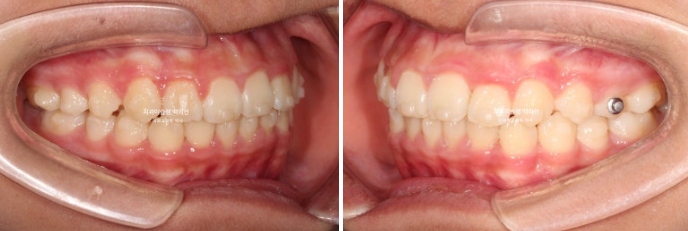

24년 1월 교정치료를 위해 온 만 10세 어린이입니다.

24.02

3년 전에 소아치과에서 앞니 부분교정을 한 적이 있다고 합니다.

그래서 위 앞니에는 중절치 두 개를 잇는 철사유지장치가 붙어있었습니다.

중심선이 약 2mm 어긋나 있고 위 앞니 치축은 한쪽으로 기울어져 있습니다.

앞니가 깊게 물리는 과개교합도 보입니다.

공간부족으로 인한 덧니가 심해 반대교합이 있습니다.